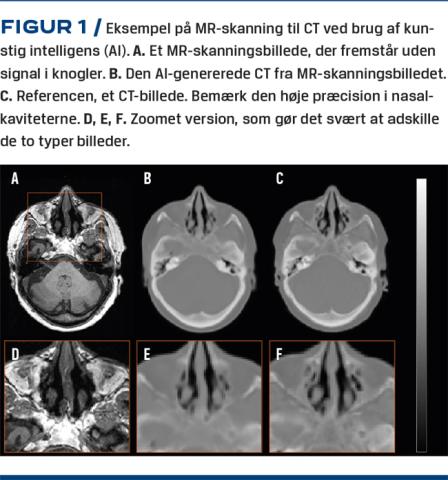

PET/MR er en nyere skanningsmodalitet med Nordens første installation på Rigshospitalet i 2011. PET/CT-skannere har høj diagnostisk sikkerhed, men PET/MR-skannerne kan være bedre til diagnostik af hjernesygdom m.m. Desværre skal man bruge CT til at korrigere PET-billederne for fotoners absorption i væv og knogler, og det kan man ikke med MR. Vi har derfor udviklet en AI-metode, som kan generere CT-lignende data fra MR-sekvenser til korrektion af PET-data og med en fejl i præcisionen på under 1% [17] (Figur 1). Systemet er implementeret i klinisk praksis til brug hos patienter med demens, så de undgår en ekstra CT, hvilket giver kortere undersøgelsestid og effektiviseringsgevinst med bedre patientkomfort og mindre stråledosis.